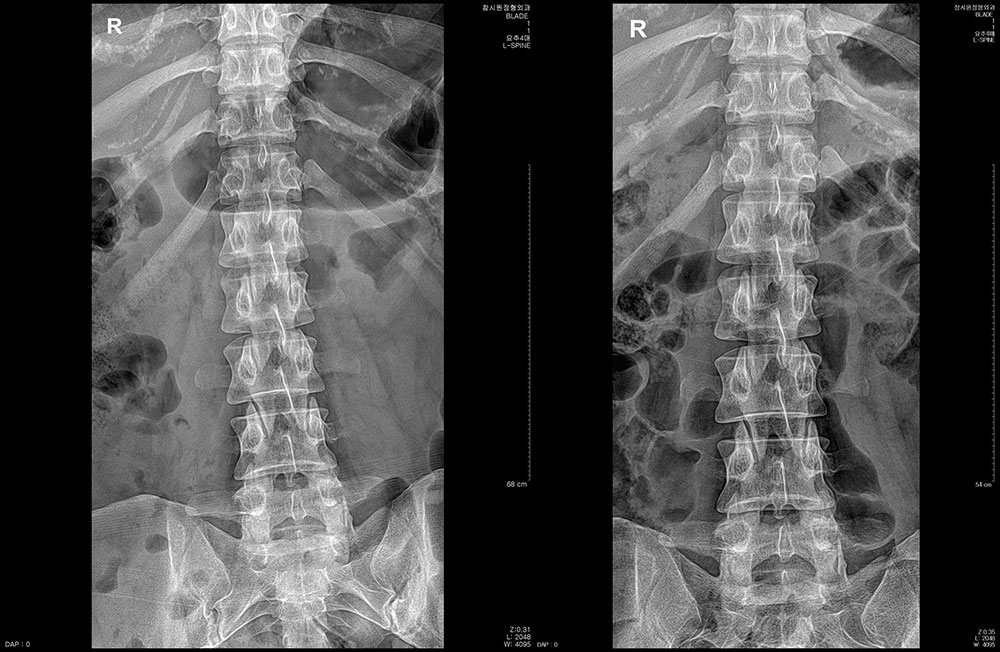

ÃÊÀ½ÆÄÁø´Ü ÇÁ·Ñ·ÎÄ¡·á ü¿ÜÃæ°ÝÆÄ µµ¼öÄ¡·á ¿ÀÇǽºÁúȯ °üÀý¿°Ä¡·á Ä¡·á Àü/ÈÄ »çÁø Ä¡·á Àü/ÈÄ »çÁø °ÅºÏ¸ñ µµ¼öÄ¡·á 10ȸ ÈÄ °ÅºÏ¸ñ µµ¼öÄ¡·á 8ȸ ÈÄ Ç㸮ÅëÁõ¡¤´Ù¸®Àú¸² µµ¼öÄ¡·á 10ȸ ÈÄ °ñ¹Ý Ʋ¾îÁü µµ¼öÄ¡·á 12ȸ ÈÄ Ã´Ãß Ãø¸¸Áõ ¹× Ç㸮ÅëÁõ µµ¼öÄ¡·á 15ȸ ÈÄ